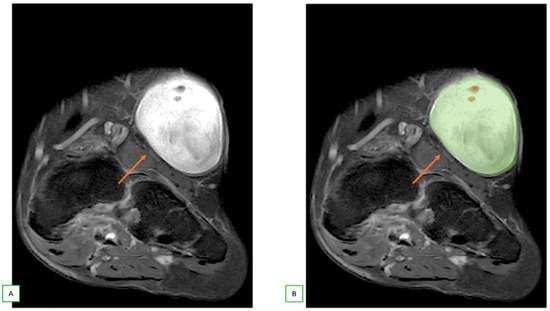

- Intraneural ganglion cysts usually occur near joints; are particularly common in the common peroneal nerve at the knee, owing to the intraarticular branch of the proximal tibiofibular joint; and appear as tubular, multiloculated cystic lesions following the course of the nerve on MRI [60,61] (Figure 16).